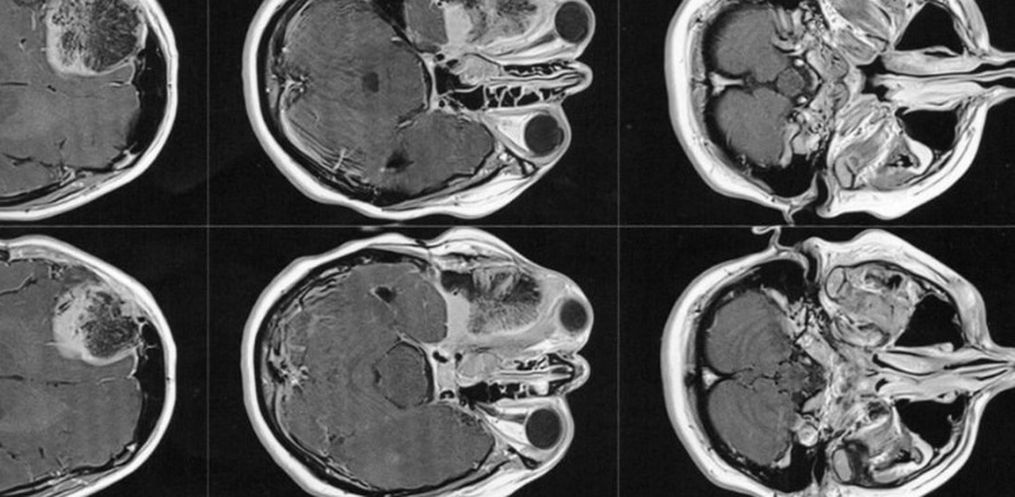

No entanto, mesmo sabendo do diagnóstico, como ela tinha o sonho de se tornar mãe, resolveu engravidar antes de passar pela cirurgia. Porém, durante a gestação, o tumor continuava crescendo, e empurrando o olho para fora. Até que um certo dia, no final da gestação, o tumor empurrou o olho de tal modo que acabou comprimindo o nervo óptico, lhe causando a cegueira do olho direito.

1 ano e 7 meses após o nascimento da Manuela (hoje com quase 4 anos), mais precisamente em dezembro de 2018, Gisele foi em busca de um neurocirurgião que estivesse apto a realizar a cirurgia. Optou-se por um médico da região, pela facilidade de locomoção. Por sua vez, por meio de exames de imagem, este médico a diagnosticou com um meningioma intraósseo (tumor cerebral benigno que se origina nas células das meninges).

Então este médico solicitou exames de imagem (ressonância magnética e tomografia) para avaliar a situação, os quais foi constatado que o meningioma ainda está ali, e que continua empurrando o olho e se expandindo para outras áreas. Trata-se de um meningioma gigante (medindo 6 x 6,6 x 6 cm), que está localizado na placa do assoalho da fossa média e anterior.